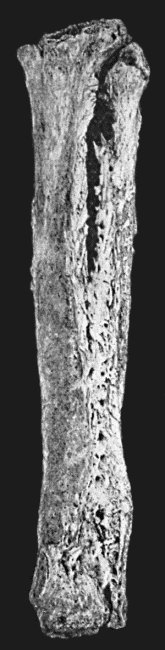

| 125. | Tuberculous Disease of Tibia | 457 |

| 126. | Diffuse Tuberculous Osteomyelitis of Right Tibia | 458 |